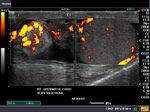

Sonography of the scrotum was done in this child who had acute swelling of the scrotum and penis. Ultrasound images reveal 1) thickening (11mm.) of the scrotal and penile skin and subcutaneous tissue and 2) marked hyperemia of the scrotum as well as the prepuce. The testes show normal appearance on sonography. These ultrasound and color doppler images are diagnostic of idiopathic scrotal edema. Images taken using a Nemio XG color doppler machine, by Joe Antony, MD.